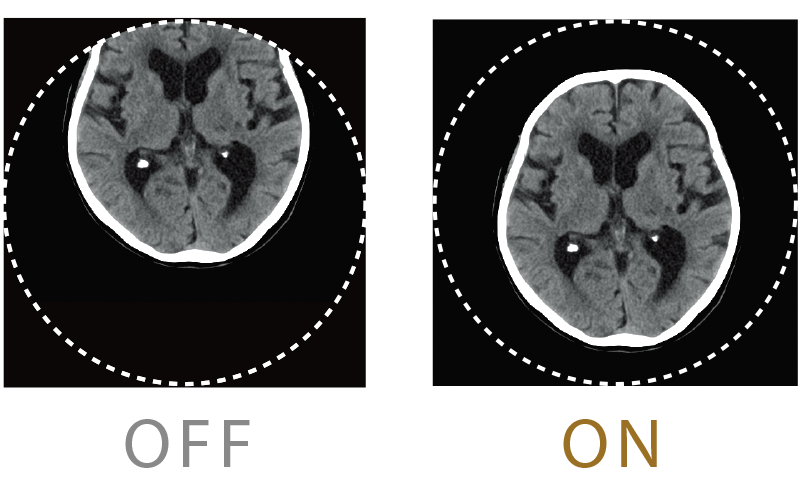

Equipped with a motion artifact correction, body movement can be compensated even after scanning. Even if the patient is out of the effective field of view, such as a patient with a kyphosis, images can be reconstructed without re-scanning in case it is within the maximum effective field of view.